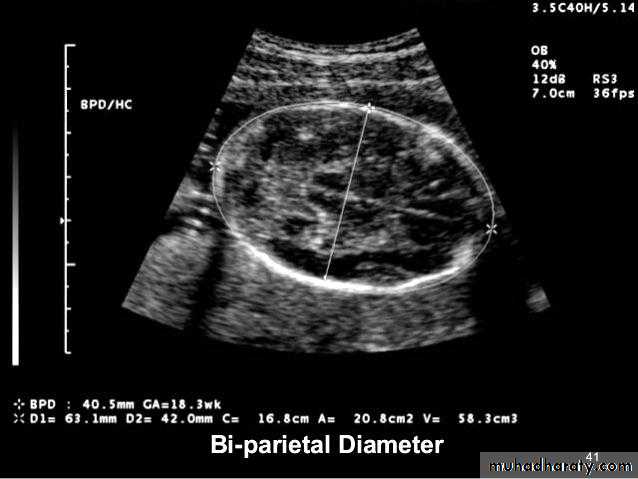

US of the obstetric & Gyne.BPD together with head circumference (HC), abdominal circumference (AC), and femur length (FL) are computed to produce an estimate of fetal weight. In the second trimester this may be extrapolated to an estimate of gestational age and an estimated due date (EDD) .

The BPD should be measured on an axial plane that traverses the thalami, and cavum septum pellucidum. The transducer must be perpendicular to the central axis of the head, and thus the hemispheres and calvaria should appear symmetric.